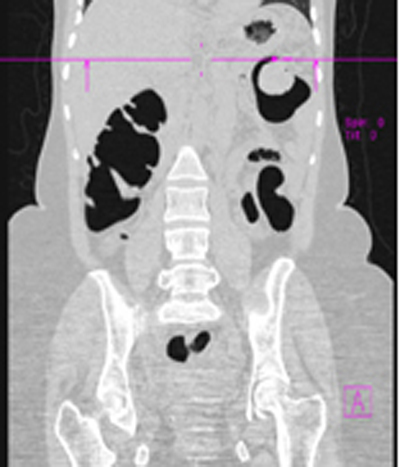

Figura Nº 3. Lesiones de aspecto submucoso

b) imagen corte coronal 2D

c) reconstrucción en 3D.